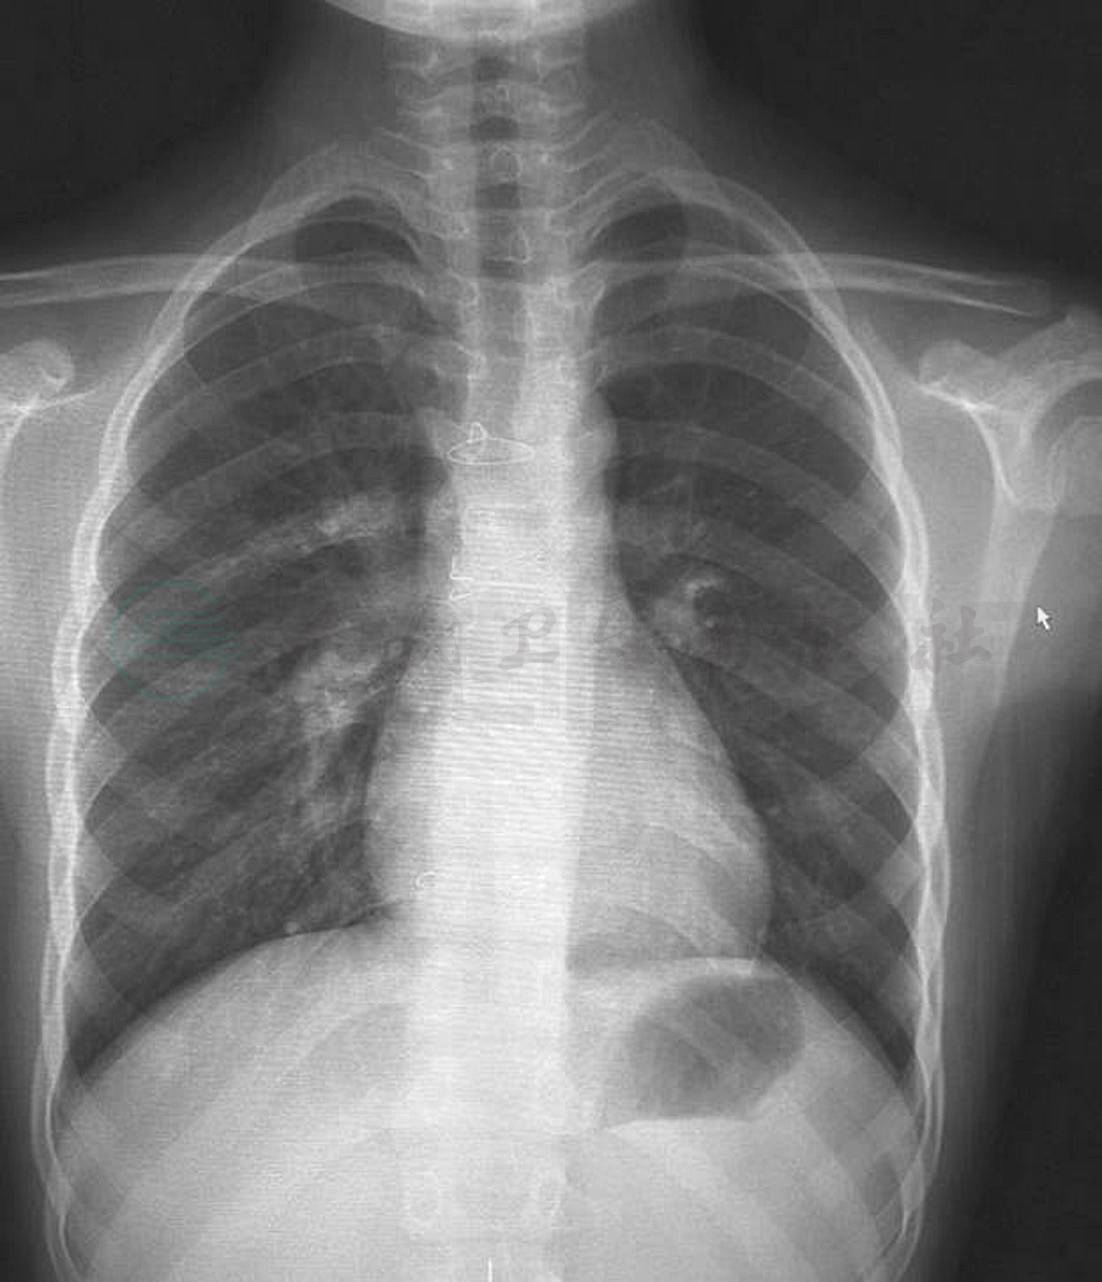

X线胸片(图1):两肺血不对称,左肺血减少,主动脉结不宽,肺动脉段平直,各房、室未见明显增大,心胸比0.48。

图1 胸部X线平片(正位):两肺血不对称,左侧明显少于右侧